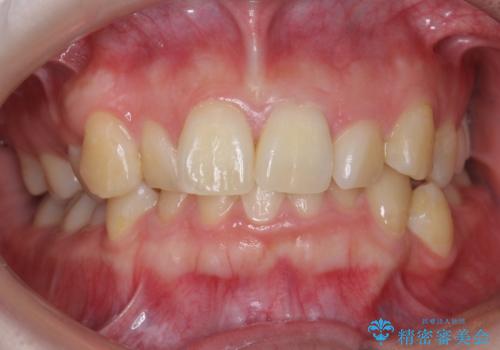

- 前歯の並びと下の歯のがたつきを主訴に来院。

左下にがたつきが集中していました。

歯を抜かずに、左上および左下の奥歯を後ろに送ることで隙間を確保しました。

左下の第一小臼歯が歯列からはみ出て、近心傾斜しており、抜歯の上ワイヤー矯正の選択肢もお話ししましたが、非抜歯で、インビザライン矯正を希望されました。左下の第一小臼歯は完全に並べることは難しいと初めから説明し、納得いただいた上で治療開始しました。